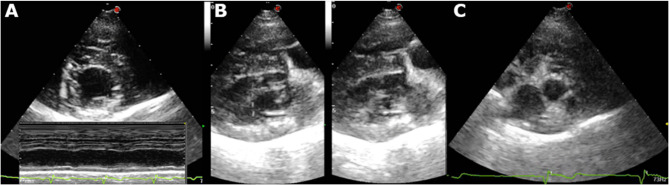

Thoracic radiographs, ECG, and echocardiography were also done at the referring veterinarian demonstrating signs of cardiomegaly, reduced myocardial systolic function, and possible congestive heart failure (CHF). At presentation, general physical examination was otherwise unremarkable with the exception of mild lethargy and weak femoral pulses. A follow-up echocardiogram performed at our hospital demonstrated reduced systolic function (Figs. 2A, B) in both B-mode and M-mode, consistent with a dilated cardiomyopathy (DCM) phenotype. Additionally, there was mild hyperechoic thickening of the left ventricular walls (Fig. 3A), mild left ventricular impaired relaxation (mitral inflow: E/A waves = 0.30/0.34 m/s), and borderline left atrial size (Fig. 3C).

Fig. 3.

A Right parasternal short axis view at the level of papillary muscles: notice the mild epicardial irregularities and generalized hyperechogenicity observed as linear/patch-like hyperechoic areas (also seen in 3B). Lower part. M-mode on the same window displaying hypokinesis of the interventricular septum and the left ventricular wall. B Right parasternal long axis 4-chamber view: marked left ventricular systolic dysfunction (left diastole, right systole) and myocardial mild hyperechoic texture. C right parasternal short axis view at the level of the left atrium and aorta: left atrial enlargement LA/Ao ratio 1.61